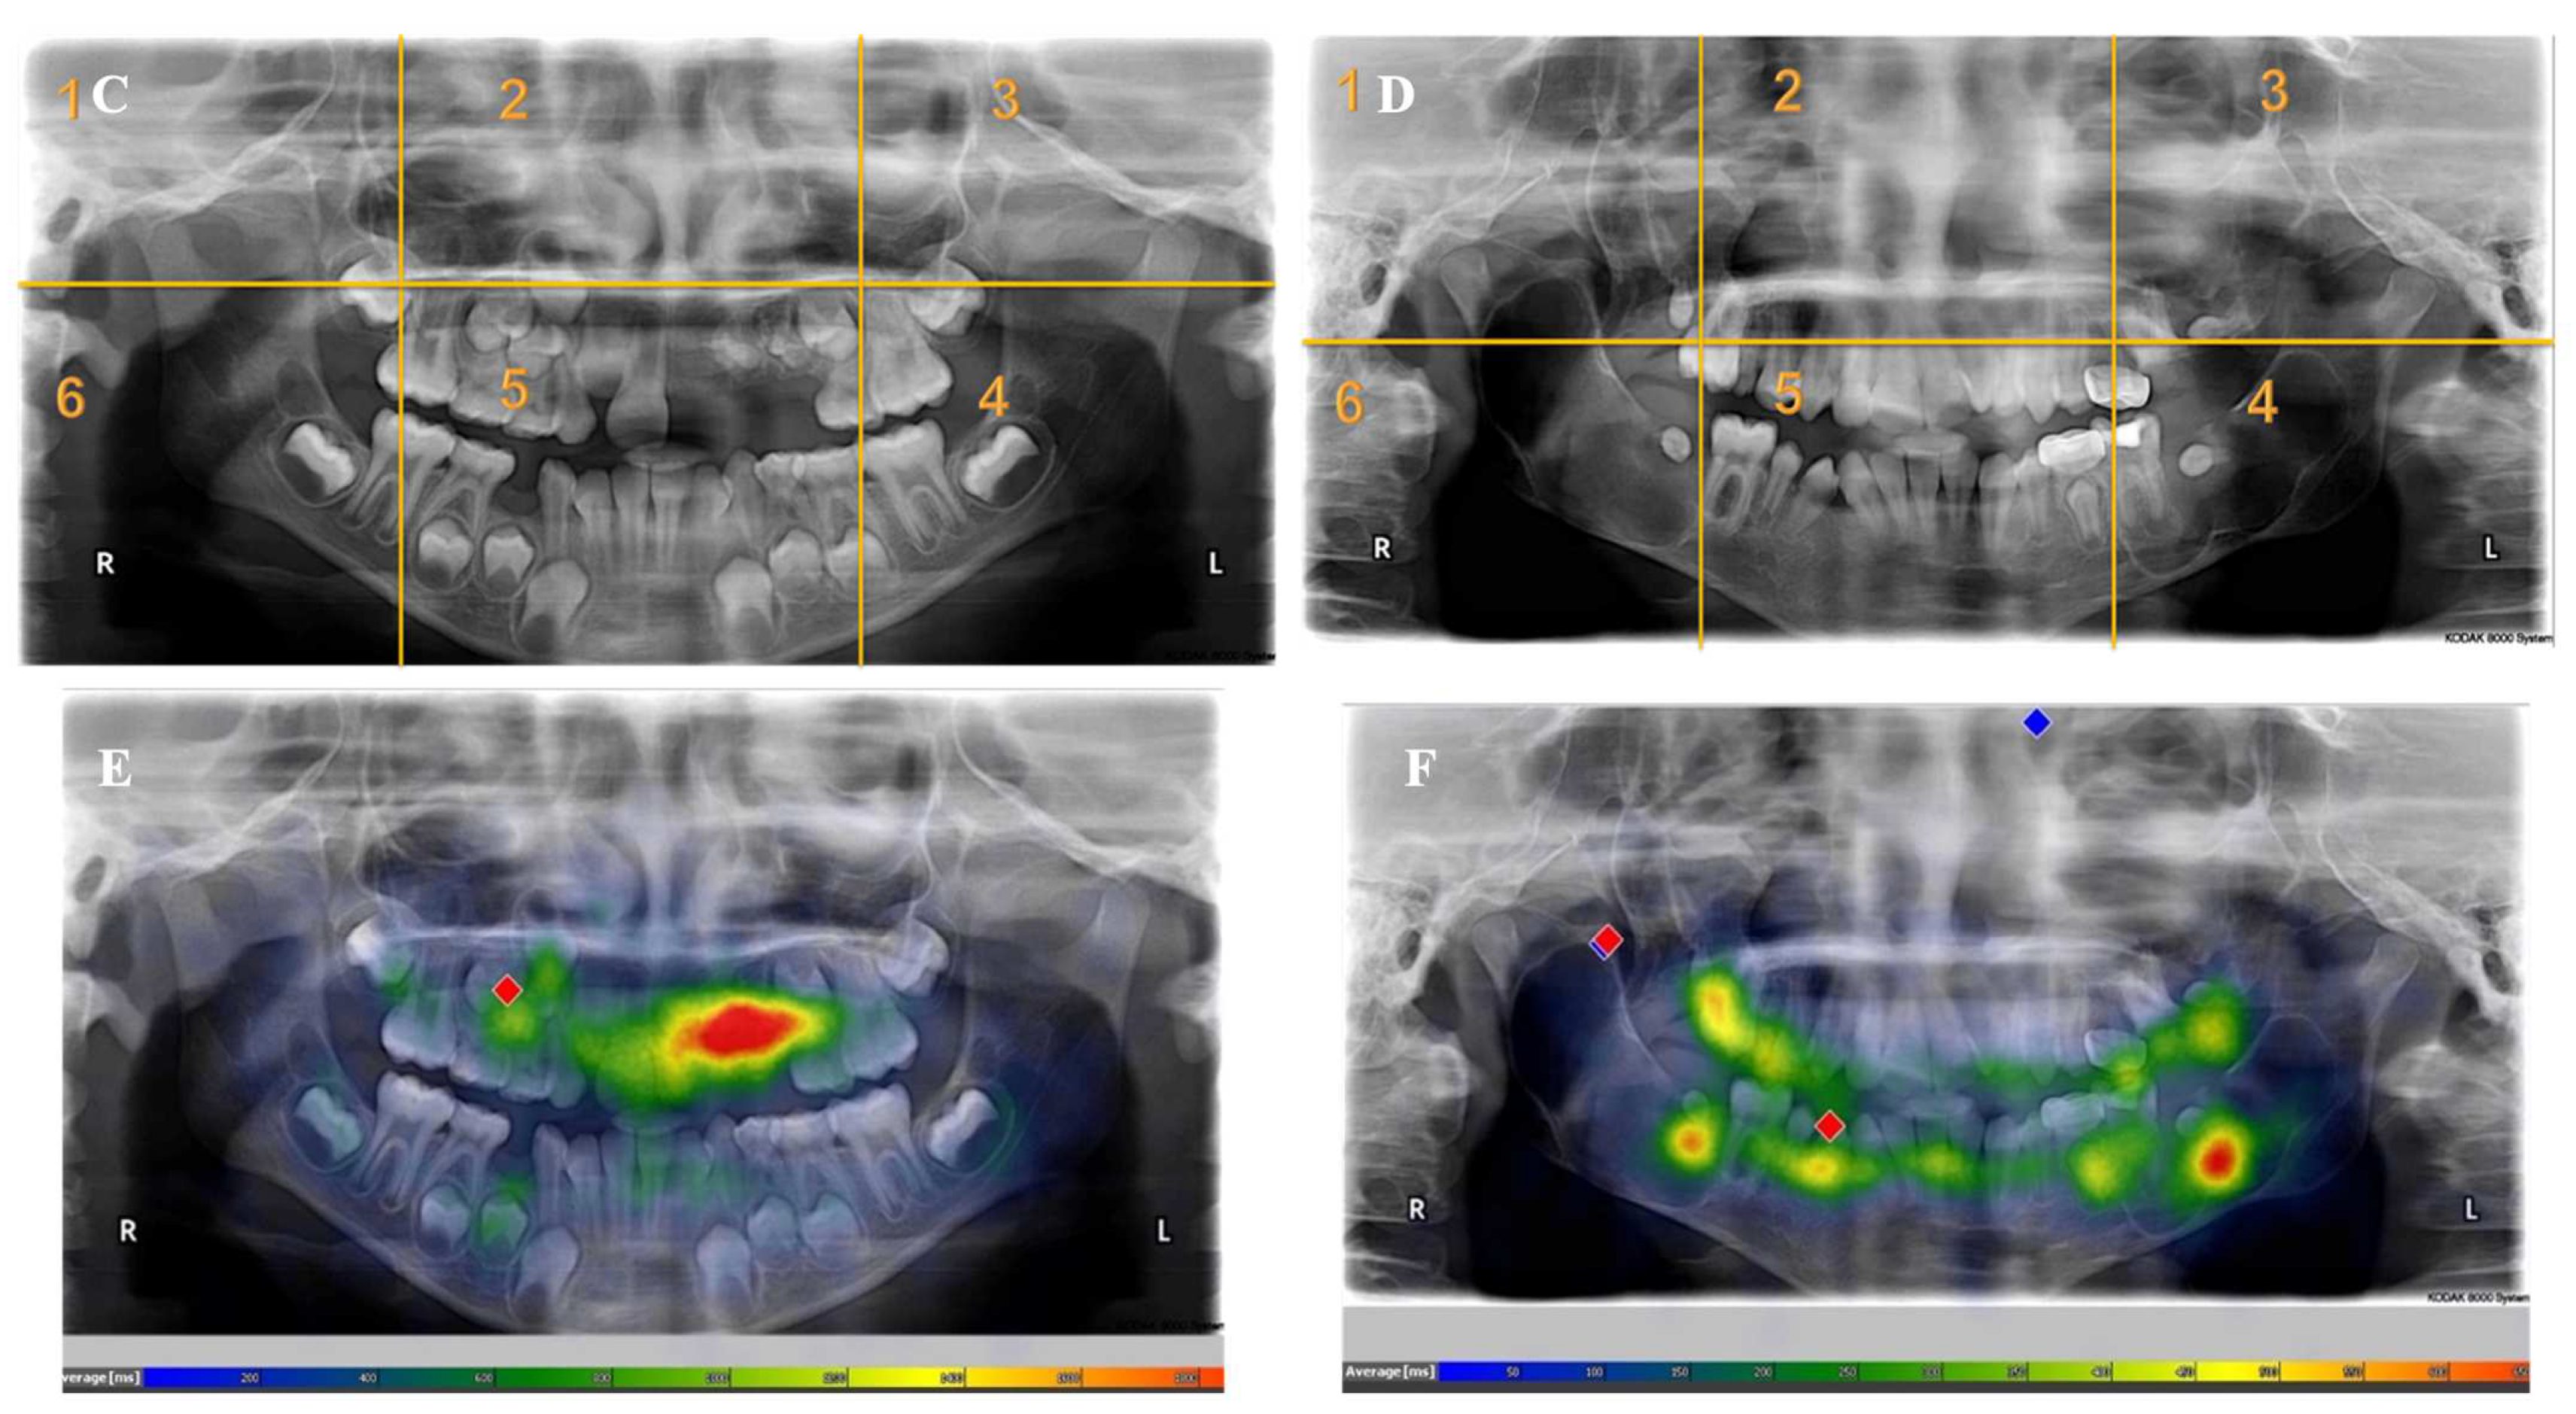

- Each panoramic radiograph displayed will be divided into sextants by yellow lines.

Appendix A. Radiographs Included in the Study